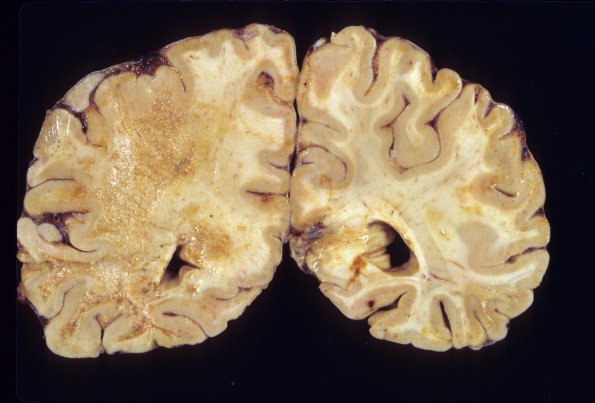

Washington University Experience | INFECTION | Viruses | PML (JC Virus) | PML - Gross Pathology | 3A4 PML (Case 3) 3

3A4 PML (Case 3) 3

Additional gross specimens of case 3.